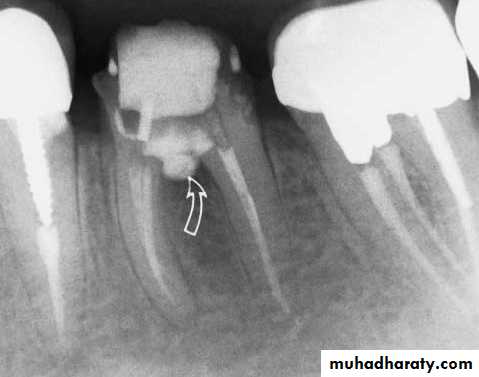

Repair of stripping perforation (arrow)

• B- Stripping perforation• Usually results from excessive flaring with files or drills.

• Over enlargement of canal

• Direction of lateral pressure distally (Gates Glidden)

Treatment:

• non-surgical treatment by immediate sealing using MTA

• surgical treatment: hemi-section, and root amputation